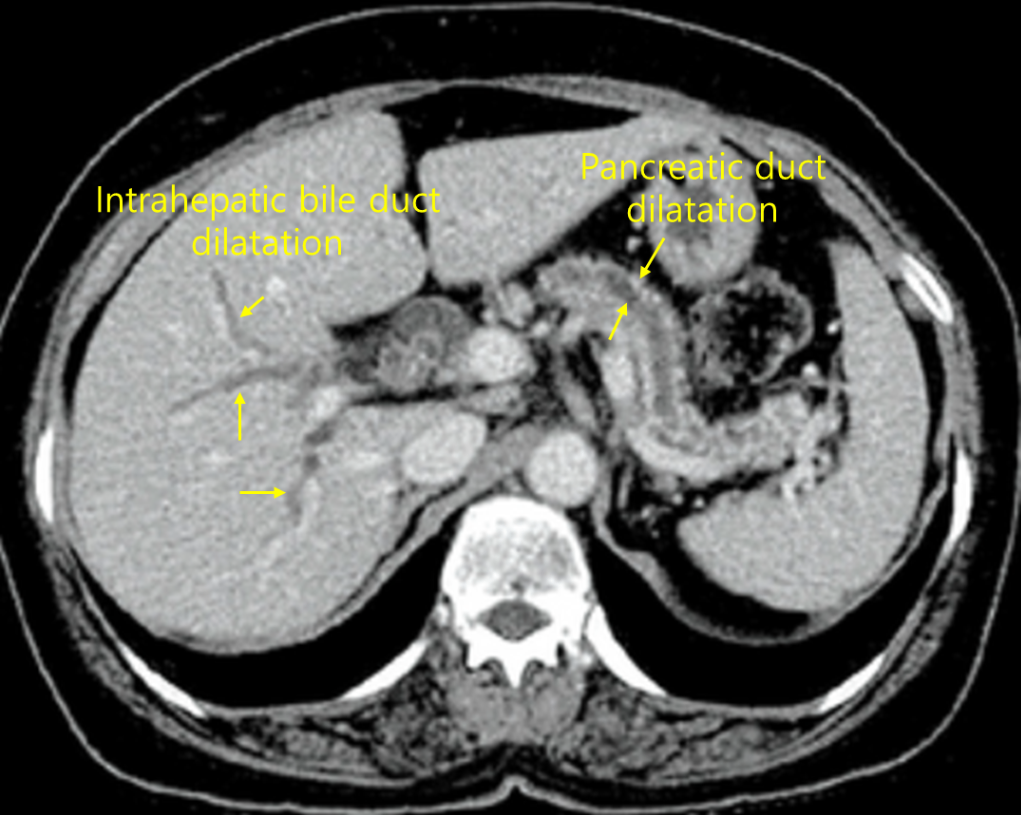

Img | CT: 간내담관, 주췌관 확장 |

소화불량, 체중감소, 최근 진단된 당뇨병, 혈액검사 상 CA19-9 상승 등으로부터 췌장암을 의심할 수 있다. T.bil, ALP 상승 및 CT 상 간내담관과 주췌관의 확장은 담관폐쇄를 의미하며 췌두부암 등 팽대부주위암에서 나타날 수 있다.

진단 | • CT: Pancreatic mass, pancreatic duct dilatation(head cancer의 경우) • MRCP: Double-duct sign(head cancer의 경우) |